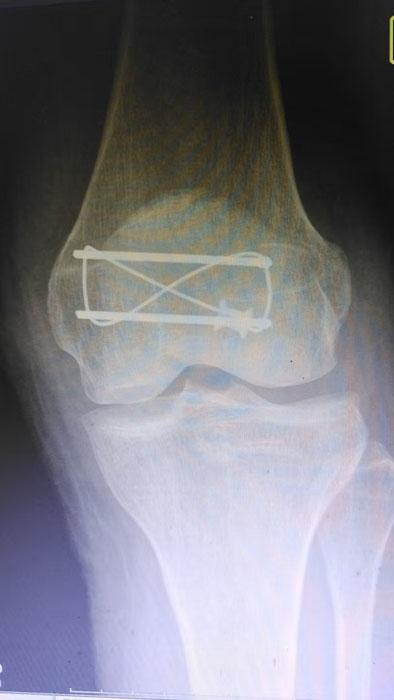

何店鎮(zhèn)中心衛(wèi)生院成功開展髕骨鋼板內(nèi)固定手術(shù)

——何店鎮(zhèn)中心衛(wèi)生院成功開展髕骨鋼板內(nèi)固定手術(shù)

隨州新聞網(wǎng)訊 (通訊員王靜、陳勇)為深入推進(jìn)緊密型醫(yī)共體建設(shè),切實(shí)讓轄區(qū)群眾在家門口就能享受到優(yōu)質(zhì)、便捷的醫(yī)療服務(wù),以醫(yī)療便民舉措為優(yōu)化營商環(huán)境注入健康活力,3月31日中午,何店鎮(zhèn)中心衛(wèi)生院(隨州市曾都區(qū)人民醫(yī)院何店分院)依托醫(yī)共體資源優(yōu)勢,特邀曾都區(qū)人民醫(yī)院脊柱創(chuàng)傷外科主任徐三軍到該院,成功為一名47歲髕骨骨折患者實(shí)施髕骨骨折切開復(fù)位內(nèi)固定手術(shù),用專業(yè)診療守護(hù)群眾健康,用務(wù)實(shí)行動踐行便民宗旨。

精湛施術(shù) 安全有序,守護(hù)患者健康

手術(shù)現(xiàn)場,徐三軍主任憑借多年積累的臨床經(jīng)驗(yàn)和嫻熟的手術(shù)技巧,精準(zhǔn)完成骨折復(fù)位、鋼板內(nèi)固定、傷口縫合等一系列關(guān)鍵操作,動作規(guī)范流暢、精準(zhǔn)高效,最大限度減少手術(shù)創(chuàng)傷。該院外科醫(yī)護(hù)團(tuán)隊(duì)全程密切配合、協(xié)同發(fā)力,嚴(yán)格按照手術(shù)規(guī)范操作,全程嚴(yán)密監(jiān)測患者心率、血壓等生命體征,及時應(yīng)對術(shù)中各類突發(fā)情況,全力保障手術(shù)安全。此次手術(shù)全程順利,術(shù)中出血量少,患者生命體征始終平穩(wěn),術(shù)后患者順利安返病房,為后續(xù)康復(fù)治療奠定了堅(jiān)實(shí)基礎(chǔ)。